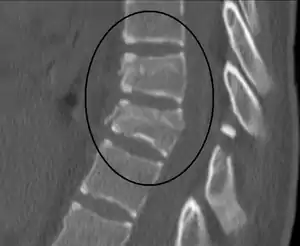

Chance fracture

A Chance fracture is a type of vertebral fracture that results from excessive flexion of the spine.[8] Symptoms may include abdominal bruising (seat belt sign), or less commonly paralysis of the legs.[4][9] In around half of cases there is an associated abdominal injury such as a splenic rupture, small bowel injury, pancreatic injury, or mesenteric tear.[3][5] Injury to the bowel may not be apparent in the first day.[10]

| A Chance fracture of T10 and fracture of T9 due to a seatbelt during an MVC. | |

The cause is classically a head-on motor vehicle collision in which the affected person is wearing only a lap belt.[2] Being hit in the abdomen with an object like a tree or a fall may also result in this fracture pattern.[11][9] It often involves disruption of all three columns of the vertebral body (anterior, middle, and posterior).[7][6] The most common area affected is the lower thoracic and upper lumbar spine.[6] A CT scan is recommended as part of the diagnostic work-up to detect any potential abdominal injuries.[5] The fracture is often unstable.[1]

A CT scan of the chest, abdomen, and pelvis is recommended as part of the diagnostic work-up to detect any potential abdominal injuries.[5][9] MRI may also be useful.[9] The fracture is often unstable.[1]